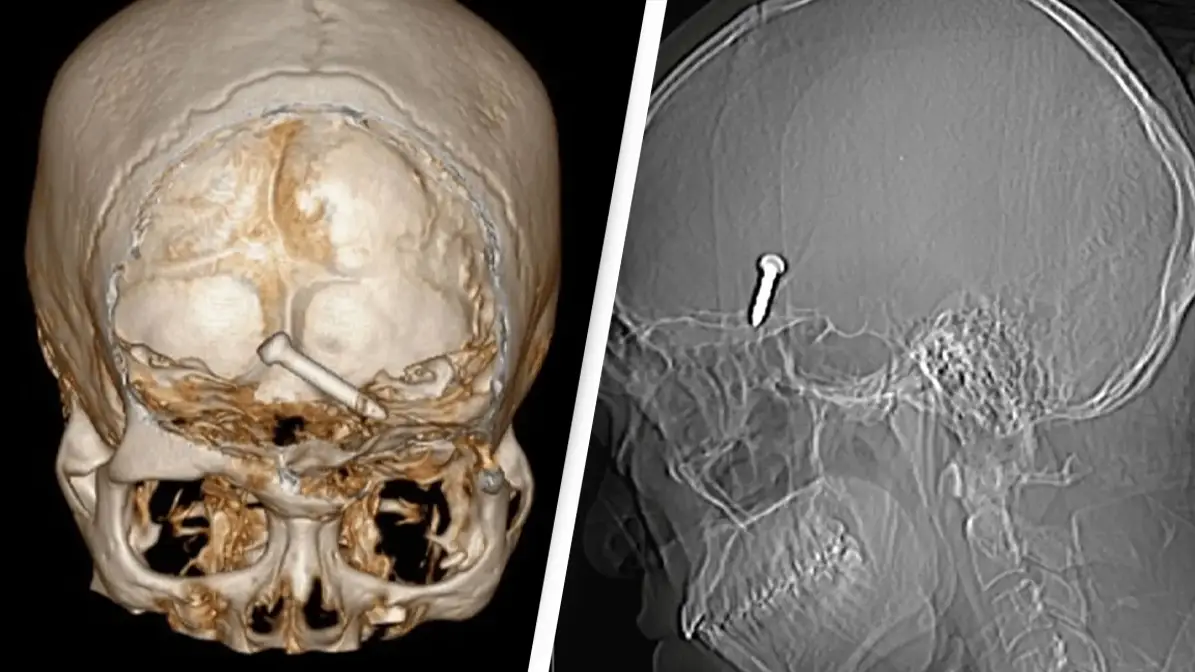

After being examined at hospital Sultanah Bahiyah in Alor Setar he was seen to by stunned doctors. A CT scan showed that the nail had become lodged in the frontal lobe of the brain, the part necessary for movement and language.

In an impressive show of their skills, medics were able to successfully remove the 3.2cm nail in a single piece and there was no active bleeding after removal of the nail.

The nail had managed to miss vital arteries and nerve, suggesting it was unlikely he would suffer from long-term nerve damage.